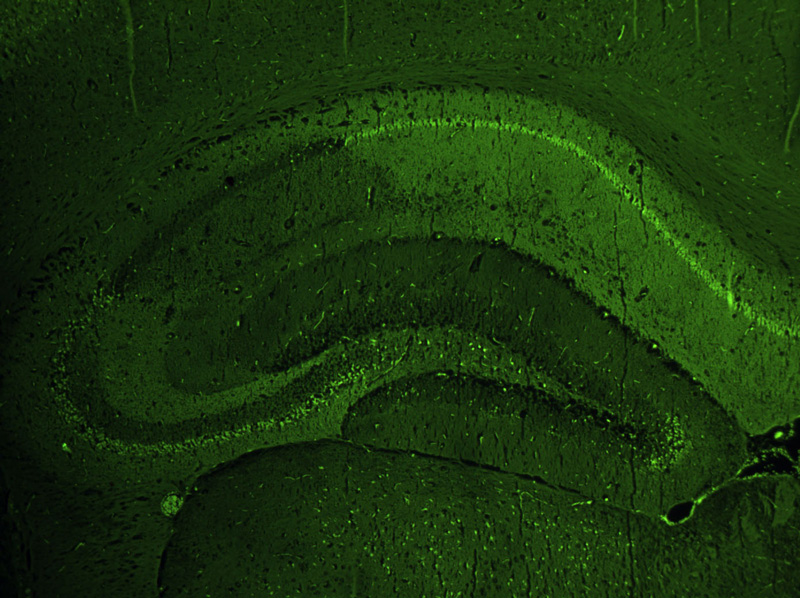

Our unit currently comprises the housing room and some laboratories of the Pharmacology department where we are able to conduct projects involving a limited number of animals (rats and mice). One of the laboratories is used for in vivo models, with two stereotaxic units for brain surgery procedures; the other laboratory has microtome and cryostat equipment for cutting histological sections which are used for all the colorimetric, immunofluorescence and immunohistochemistry assays, cell degeneration assays, and in situ hybridisation for detecting levels of expression of specific mRNAs. After histological sections have been viewed under the microscope, the images can be analysed. We also have a laboratory equipped for performing implantation surgery of brain dialysis probes (mice and rats) and for obtaining samples from freely-moving animals; a further laboratory is used for assaying neurotransmitters and/or substances derived from brain dialysate.

• protein expression of specific antigens through immunohistochemical and immunofluorescence assays on cell cultures, primary cultures and histological sections;

• genic expression by in situ hybridization and quantitative PCR;

AF-IF Immunofluorescence of an antigen on histological sections or on primary cultures: 10 slides (favourable rates can be arranged according to the number of samples to be examined and slides required) 280.00 + cost of antibody